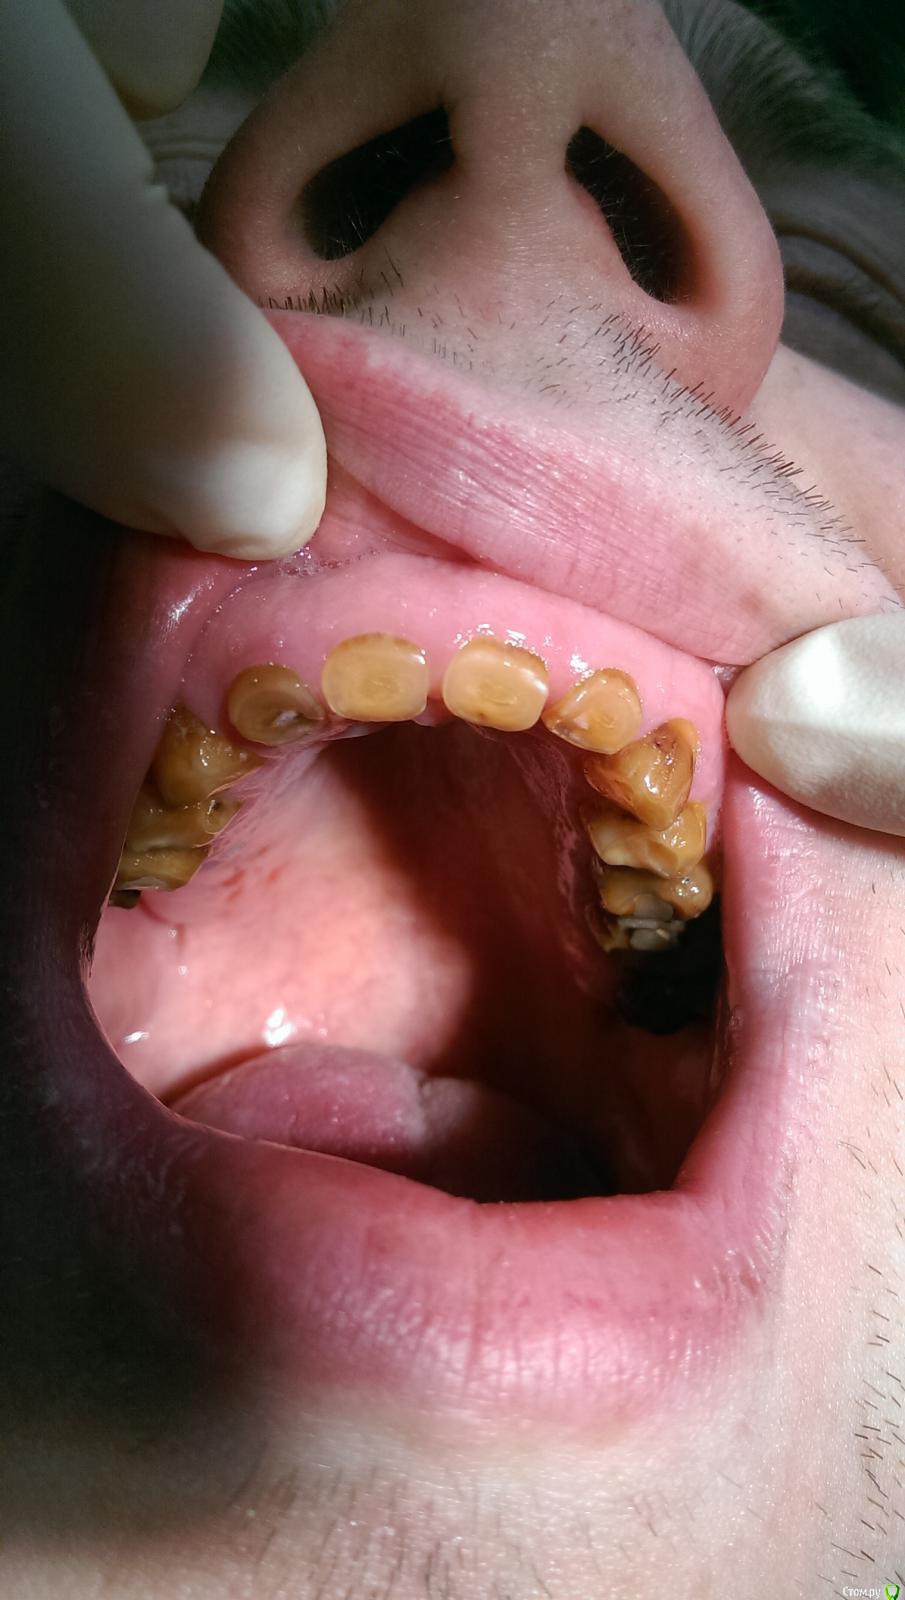

Ром@н Опубликовано 12 мая, 2015 Автор Поделиться Опубликовано 12 мая, 2015 Вот пациент вернулся и даже сделам ОПТГ Ссылка на комментарий

DR.P Опубликовано 19 декабря, 2014 Поделиться Опубликовано 19 декабря, 2014 (изменено) Интересный случай. Напишу краткий протокол лечения и варианты:1) измеряем физ покой, и высоту его прикуса. Если разница этих значений больше 2-3 мм - стираемость - необходимо повышать прикус.2) Если 2-3 мм - значит стираемость компенсаторная, то есть с зубоальвеолярным выдвижением. В случае 1) культевые вкладки и коронки (необходимо вернуть высоту прикуса)В случае 2) хирургическое удлинение зубов, коронки Изменено 19 декабря, 2014 пользователем DR.P Ссылка на комментарий

chervoncevdaniil Опубликовано 21 декабря, 2014 Поделиться Опубликовано 21 декабря, 2014 Мне кажется тут явно снижение высоты прикуса компенсировано,взгляните на мощный альвеолярный отросток.Не простая ситуация у пациента,без грамотной хирургии будет сложно Ссылка на комментарий

Ром@н Опубликовано 21 декабря, 2014 Автор Поделиться Опубликовано 21 декабря, 2014 я просто к тому будет ли фиксироваться вкладка в канале,т.к какие пломбы только не ставил все держались недолго - я к тому что будет ли фиксация Ссылка на комментарий